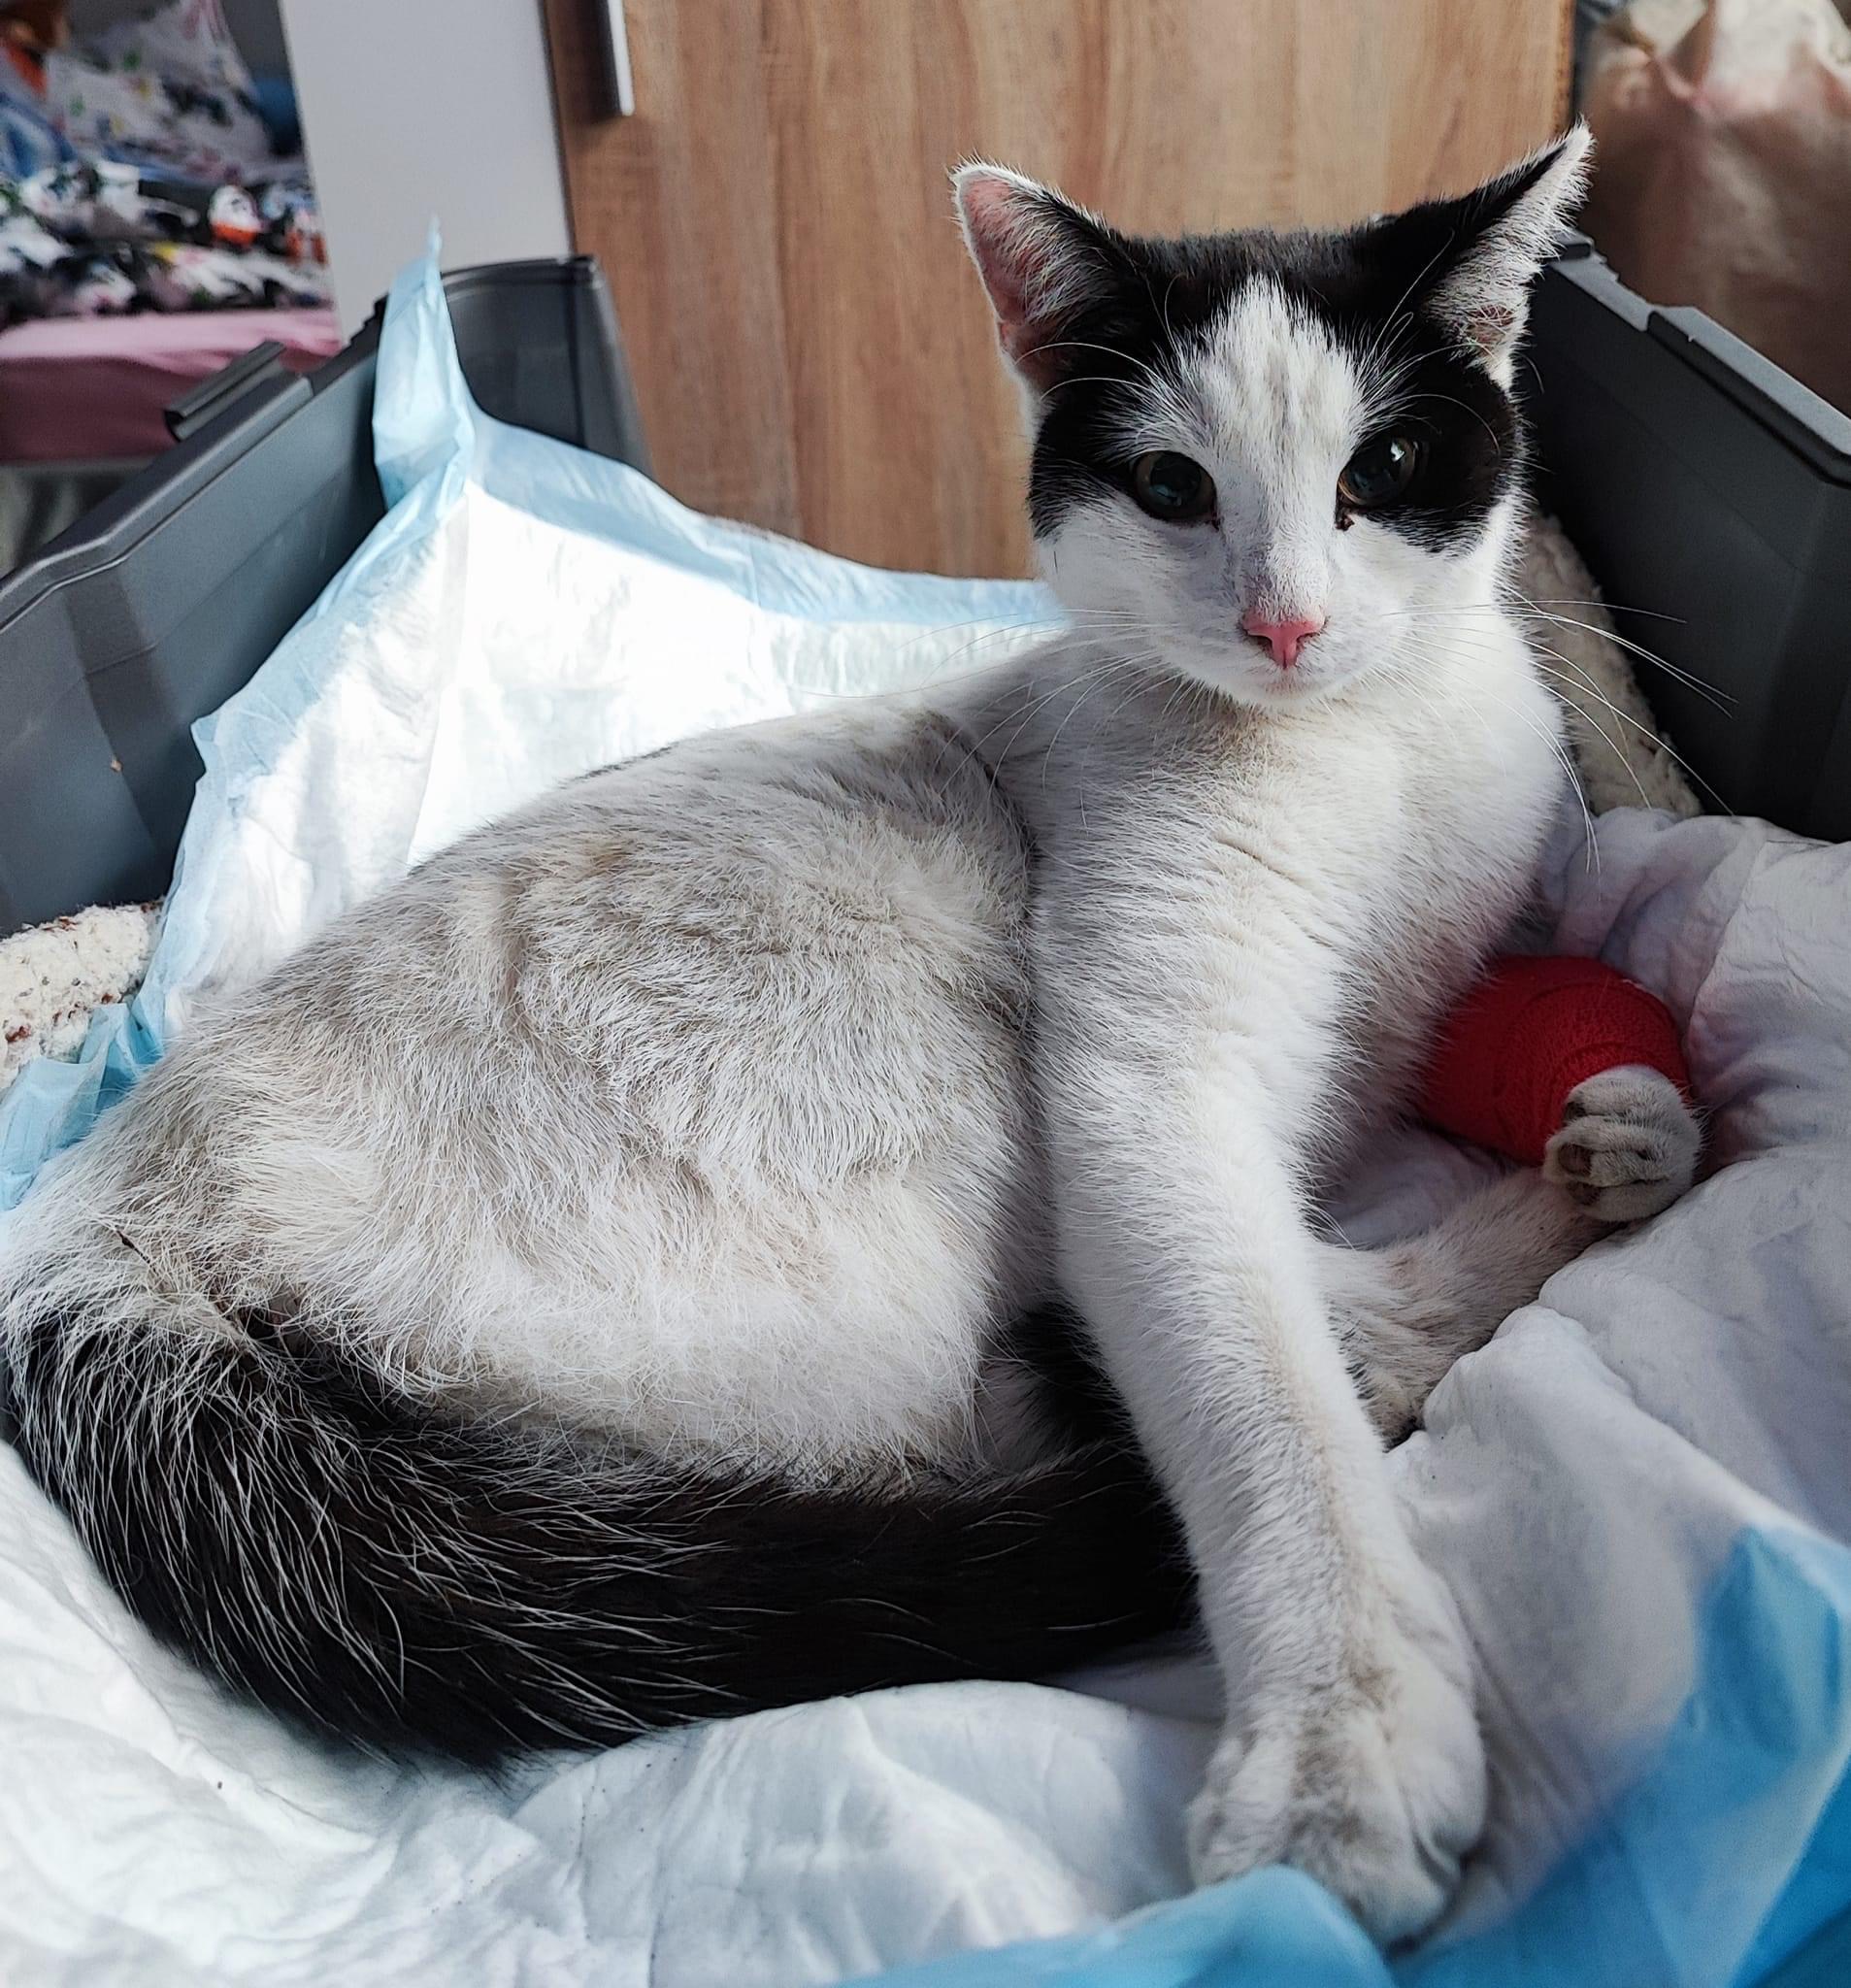

25.03.2023: Unsere Lucy hat die erste Nacht gut überstanden. Sie hat gut geschlafen, hat heute Früh gepullert und gekackert. Zwar noch unter sich, weil sie noch nicht auf die Toilette gehen kann aber es funktioniert alles. Gegessen hat sie super und das Reconvales mag sie sehr. Ihre Wunde sieht noch sehr geschwollen aus, aber das wird besser in den nächsten Tagen. Alles in allem sind wir sehr zufrieden.

03.04.2023: Heute war unsere Lucy wieder beim Tierarzt. Es wurden die Fäden gezogen. Ein paar Tage muss sie noch ihren Trichter tragen, dann darf er entfernt werden. Ein Blutbild wurde heute auch wieder gemacht. Ihre Werte werden immer besser. Eines ihrer Beinchen macht uns noch ein wenig Sorgen. Damit tritt sie nicht richtig auf. Sie versucht es aber immer wieder. Sie geht selbstständig auf die Toilette und brauchte keine Inkontinenzunterlagen mehr.